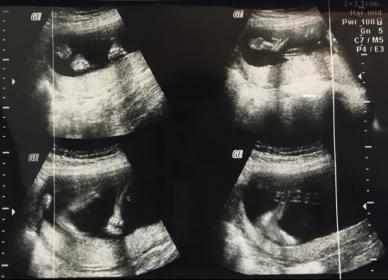

I am 20 weeks and 3 days. I had an anomaly scan today but i am not sure. I need you opinions regarding the gender of the baby. Here is my scan from today. Attachment 33751

No gender here. Do you have any side view shots from 12-14 weeks?

I don't see any gender clues in these shots either. Sorry.

Thank you for your replies GirlieCat and Claire33. I had another scan today. It's a boy : )